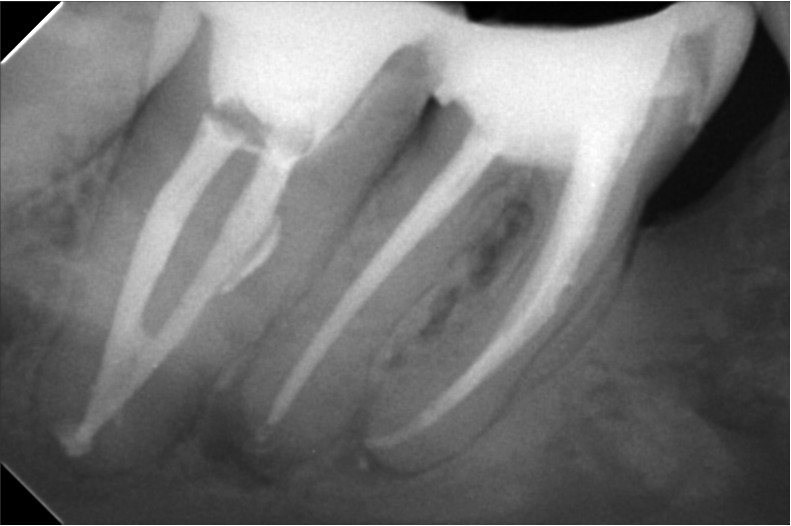

علاج الجذور يعد فرع من فروع طب الأسنان الذي يعمل على معالجة مشكلات الجذور التي تساعد على توفير الحماية والتغذية داخل الأسنان من التعرض لأي عوامل خارجية مثل: الأطعمة الساخنة والباردة هناك العديد من التقنيات التي ساعدت في علاج الجذور و التي توفرها مركز أوبال للأسنان, ومنها:جهاز الاشعة الثلاثية الابعاد , جهاز الميكروسكوب, أدوات تنظيف القنوات العصبية واخيرا حشو القنوات العصبية فكل منها لها دور مهم في عملية علاج الجذور فالاشعة الثلاثية الأبعاد تساعد في رسم خريطة دقيقة للقنوات العصبية أما الميكروسكوب فهو يعمل على توضيح الرؤية, تتيح أدوات تنظيف القنوات العصبية لأول مرة التعامل مع القنوات الضيقة والملتوية بشدة وتعد حشو القنوات العصبية عن طريق الحقن من أحدث التقنيات الطبية التي تضمن نجاح نجاح علاج الجذور أصعب الحالات من الجلسة الأولى فهي تعمل على إحكام غلق القنوات الأساسية وخصوصا الفرعية والتأكد من انها خالية من البكتيريا.